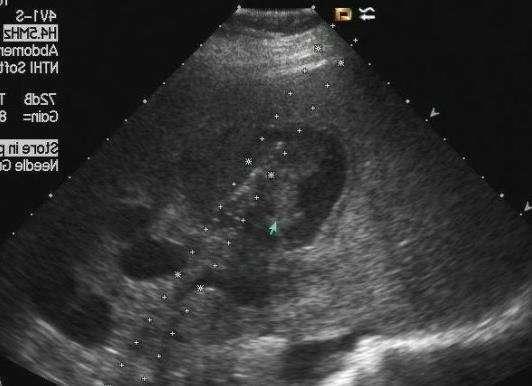

案例图:乙肝病史十年 超声显示肝实质回声增粗,增强

所以,根据这位读者是一位乙肝患者,近期又有脸黄症状,可优先排查肝功能、肝脏B超、病毒载量等指标。对于健康人出现脸黄,比如读者的家人是没有感染乙肝的情况,要优先排查以上非疾病原因,然后才是疾病原因引起。